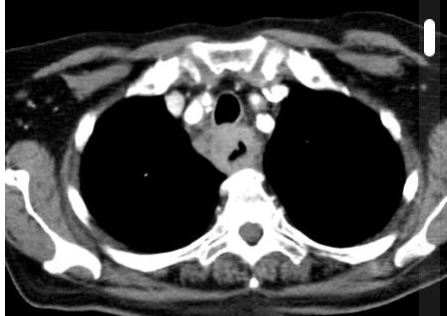

2 anos, masculino

Cisto de duplicação esofágico

Predleção por meninos; diagnosticados na infância

Em geral assintomáticos; podem provocar estridor

Mais comuns no esôfago distal; geralmente não comunicam com a luz do esôfago;

TC: Cisto com densidade de líquido, margens bem definidas que podem realçar com contraste; podem complicar com hemorragia, infecção: nível liquido, espessamento parietal.